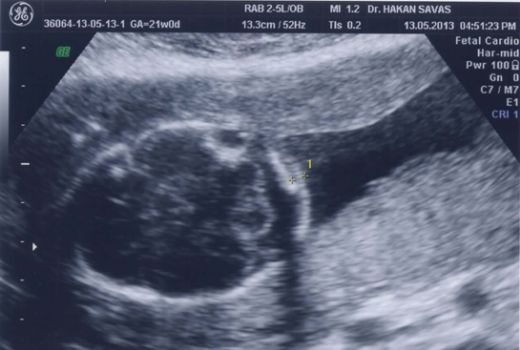

Hamilelik sürecinde yapılan ultrasonografik incelemelerde, fetüsün fiziksel yapısında bazı anormallikler gözlemlenebilir. Bu anormallikler arasında;

Down sendromu, genetik bir bozukluk olup, genellikle 21. kromozomun üç kopyası bulunmasıyla ortaya çıkar. Anne karnındaki belirtiler, genellikle ultrason incelemeleri sırasında tespit edilebilir. Bu belirtiler arasında, fetal boyutun beklenenden küçük olması, ense kalınlığının artması ve bazı organların gelişiminde anormallikler yer alabilir.

Ultrason İncelemeleri

Ultrason incelemeleri, Down sendromunun belirtilerini tespit etmekte önemli bir rol oynar. Özellikle 12. haftada yapılan nuchal translucency (ense kalınlığı) ölçümü, risk değerlendirmesinde kritik bir göstergedir. Eğer ense kalınlığı normalden fazla çıkarsa, genetik danışmanlık önerilebilir. Bunun yanı sıra, fetal kalp anormallikleri ve diğer fiziksel gelişim sorunları da ultrason ile gözlemlenebilir.